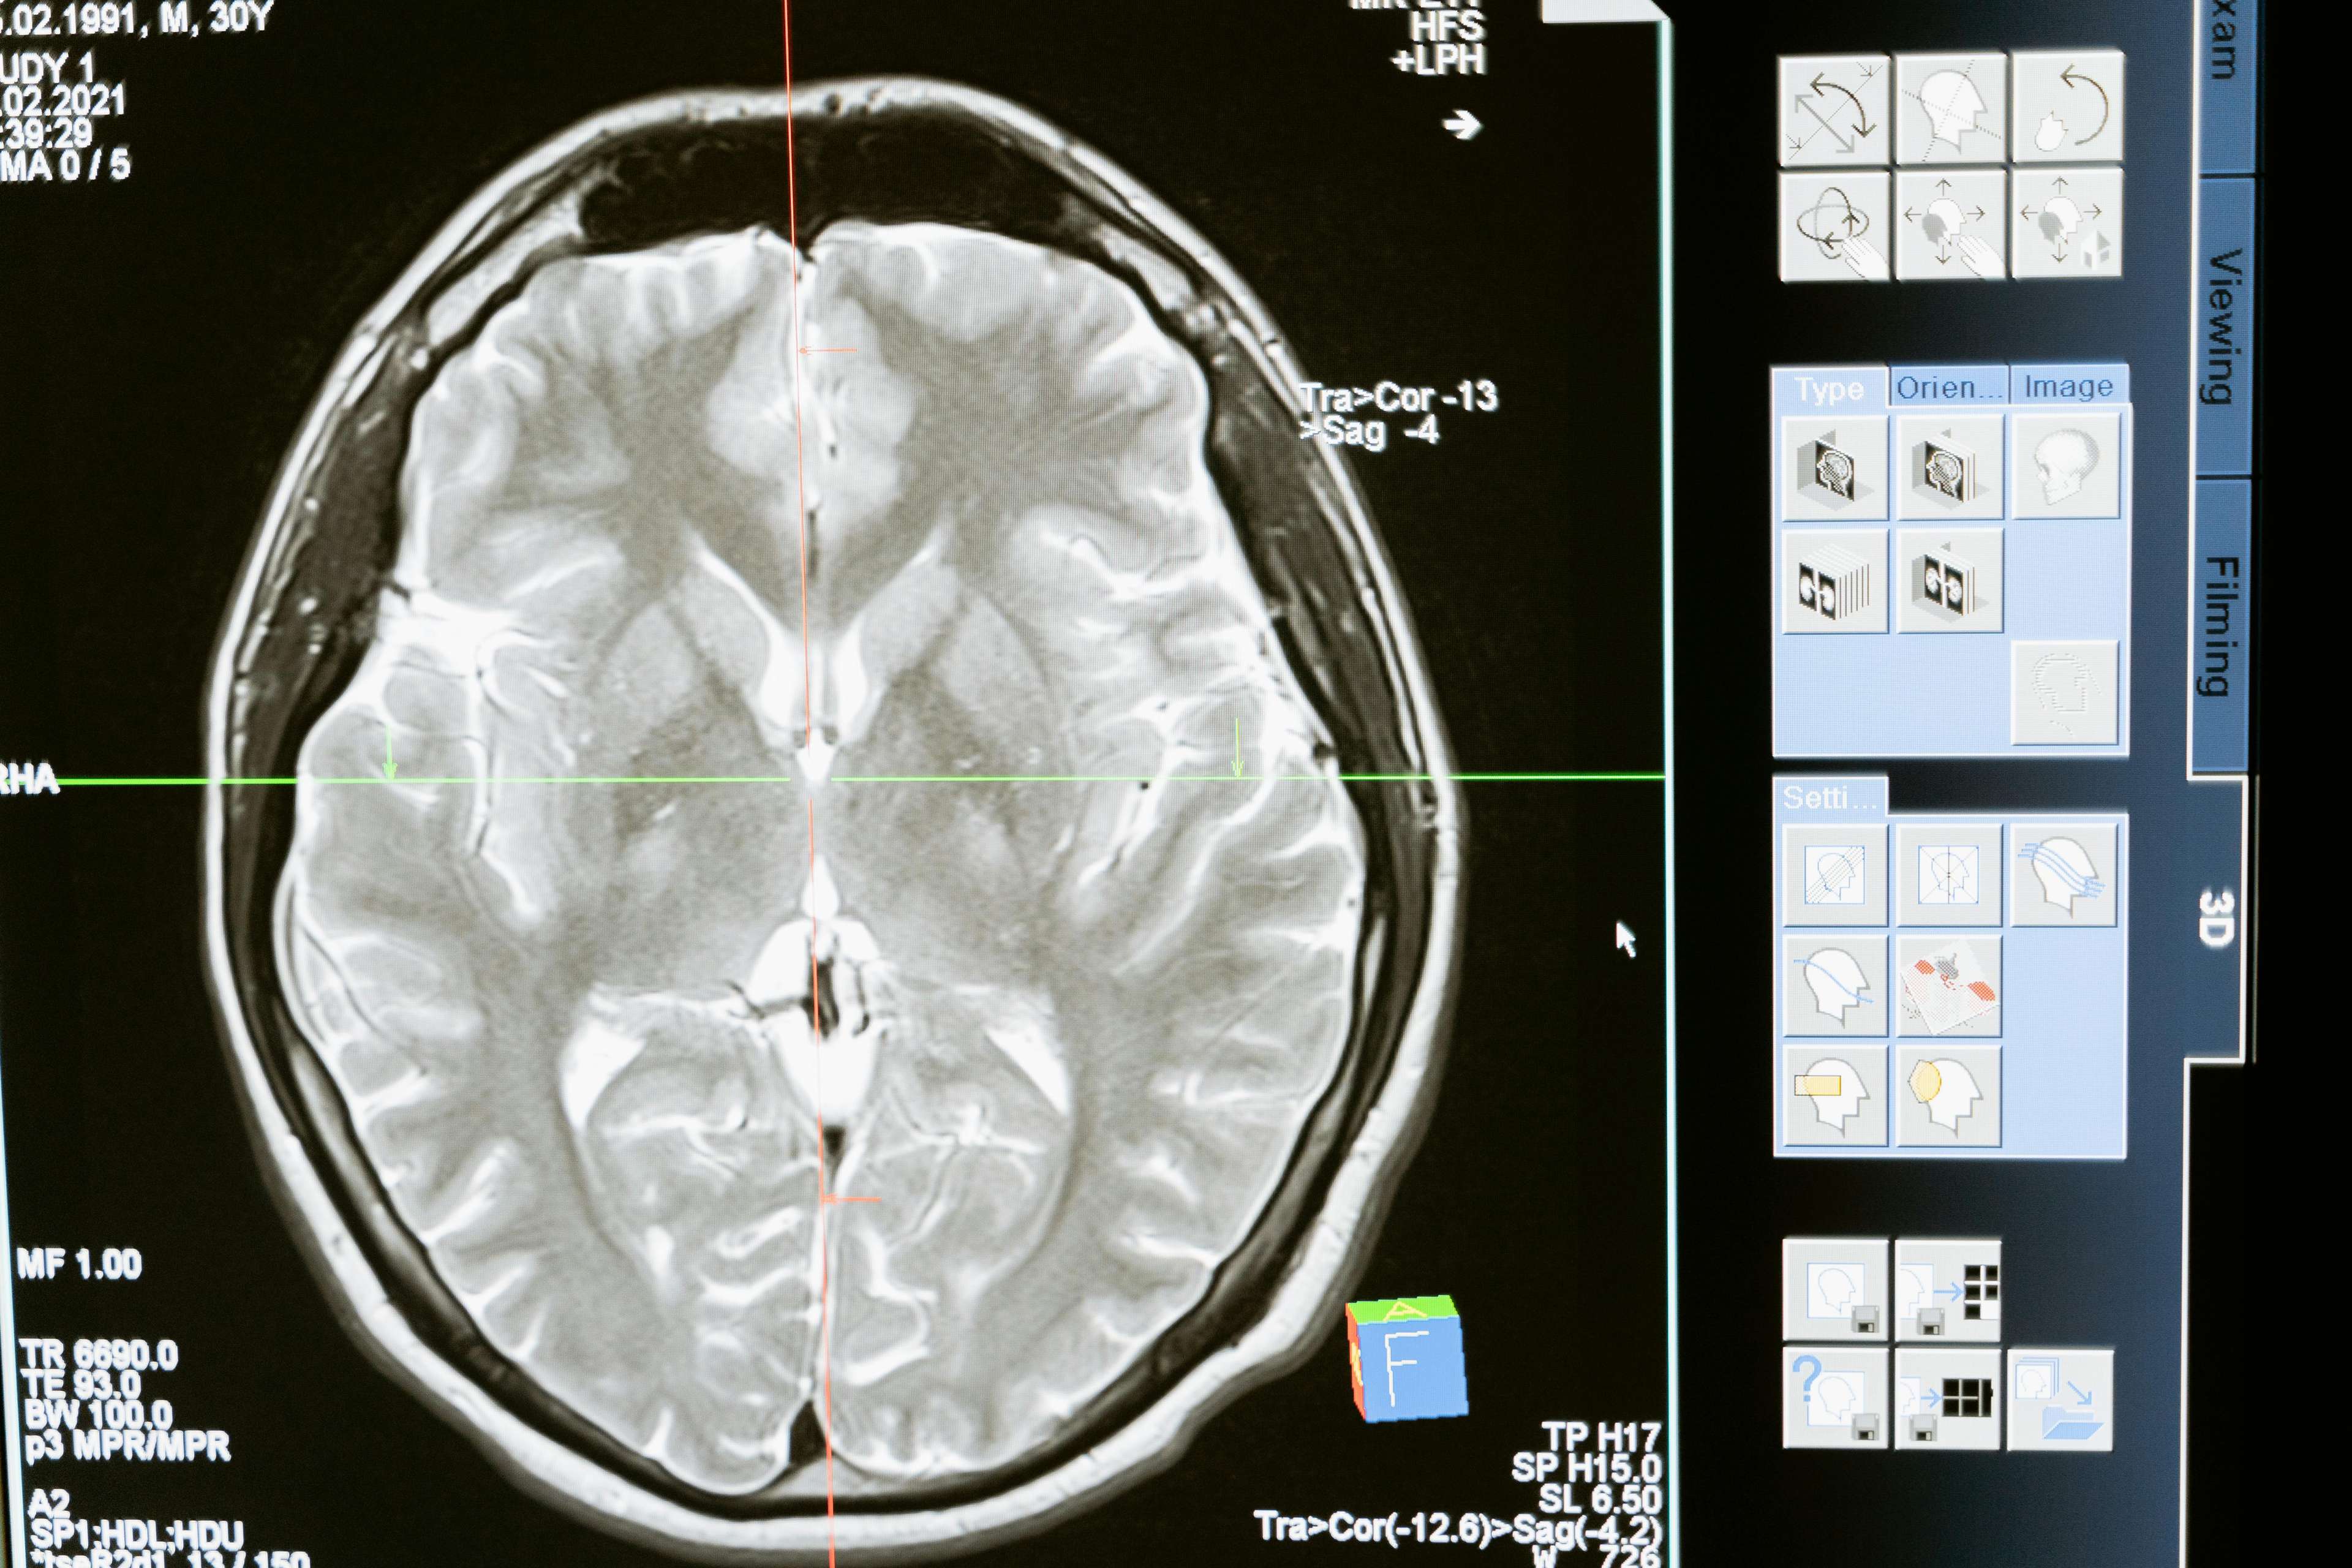

Ang deep brain stimulation ay isang surgical procedure na kinabibilangan ng pagtatanim ng isang device na nagpapadala ng mga electrical impulses sa mga partikular na bahagi ng utak. Ang makabagong paggamot na ito ay naging instrumento sa pamamahala ng isang hanay ng mga kondisyon, kabilang ang sakit na Parkinson, dystonia, obsessive-compulsive disorder, at epilepsy. Sa pamamagitan ng pag-target sa mga partikular na bahagi ng utak, ang malalim na pagpapasigla ng utak ay maaaring makatulong sa pag-regulate ng abnormal na aktibidad ng utak, pagpapagaan ng mga sintomas at makabuluhang pagpapabuti ng kalidad ng buhay. Ang mga resulta ay walang kapansin -pansin - ang mga pasyente na dating nakakulong sa kanilang mga tahanan ay nakakapaglakad, tumakbo, at mabuhay nang buong buhay.